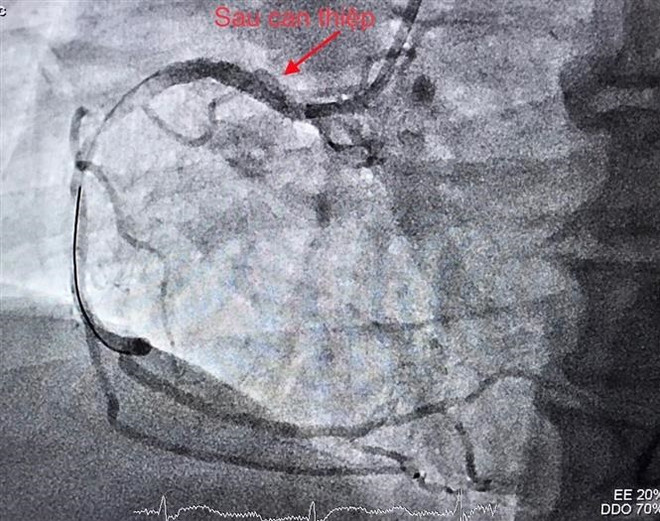

Mạch vành tái thông sau can thiệp. (Ảnh: TTXVN phát)

Bệnh nhân được nong động mạch vành bị tắc và tiến hành đặt giá đỡ (stent), giúp tái lập dòng máu nuôi tim.

Ngay sau đó, các bác sỹ can thiệp thông tắc động mạch não giữa bên phải. Các cục huyết khối được gắp ra, tái thông mạch máu bị tắc trong thời gian 20 phút.

Kết quả chụp cộng hưởng từ kiểm tra ngày hôm sau cho thấy mạch máu não bị tắc đã tái thông tốt.